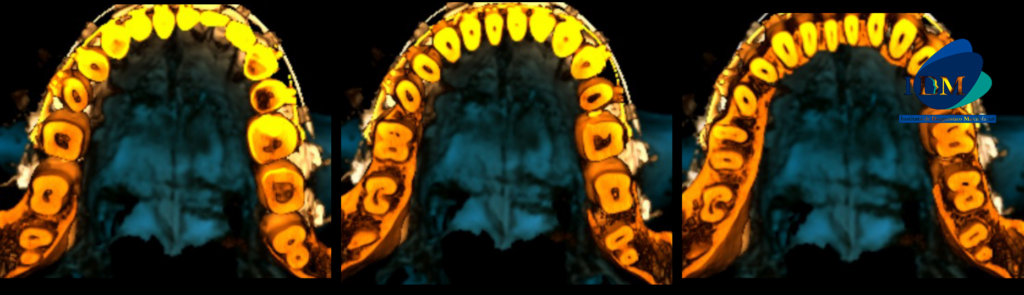

CORTES TRANSAXIALES

A la evaluación de la tomografía volumétrica (cone beam) en los cortes axiales (Figura 2), tangenciales (Figura 3) y en la reconstrucción 3D (Figura 4) se observa en la pieza 47 la configuración del conducto radicular en forma de “C” desde tercio cervical hasta apical.